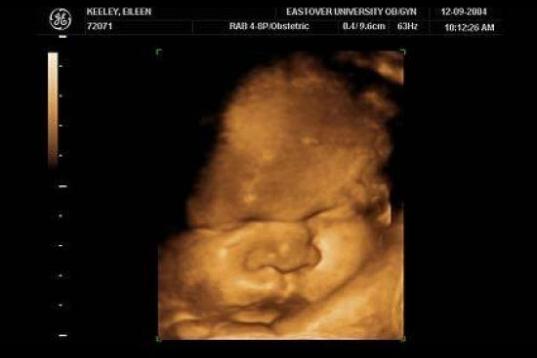

En esta galería puedes ver en fotos como es el desarrollo de un feto de semana en semana:

Desarrollo del feto, en fotos